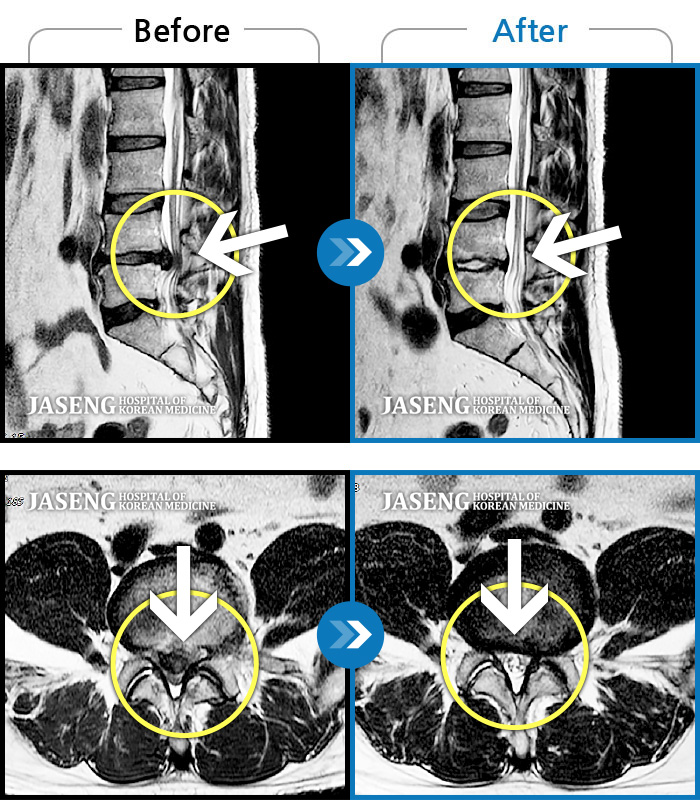

MRI 치료사례

허리 통증과 다리 저림이 심해 걷지도 앉지도 못하겠어요